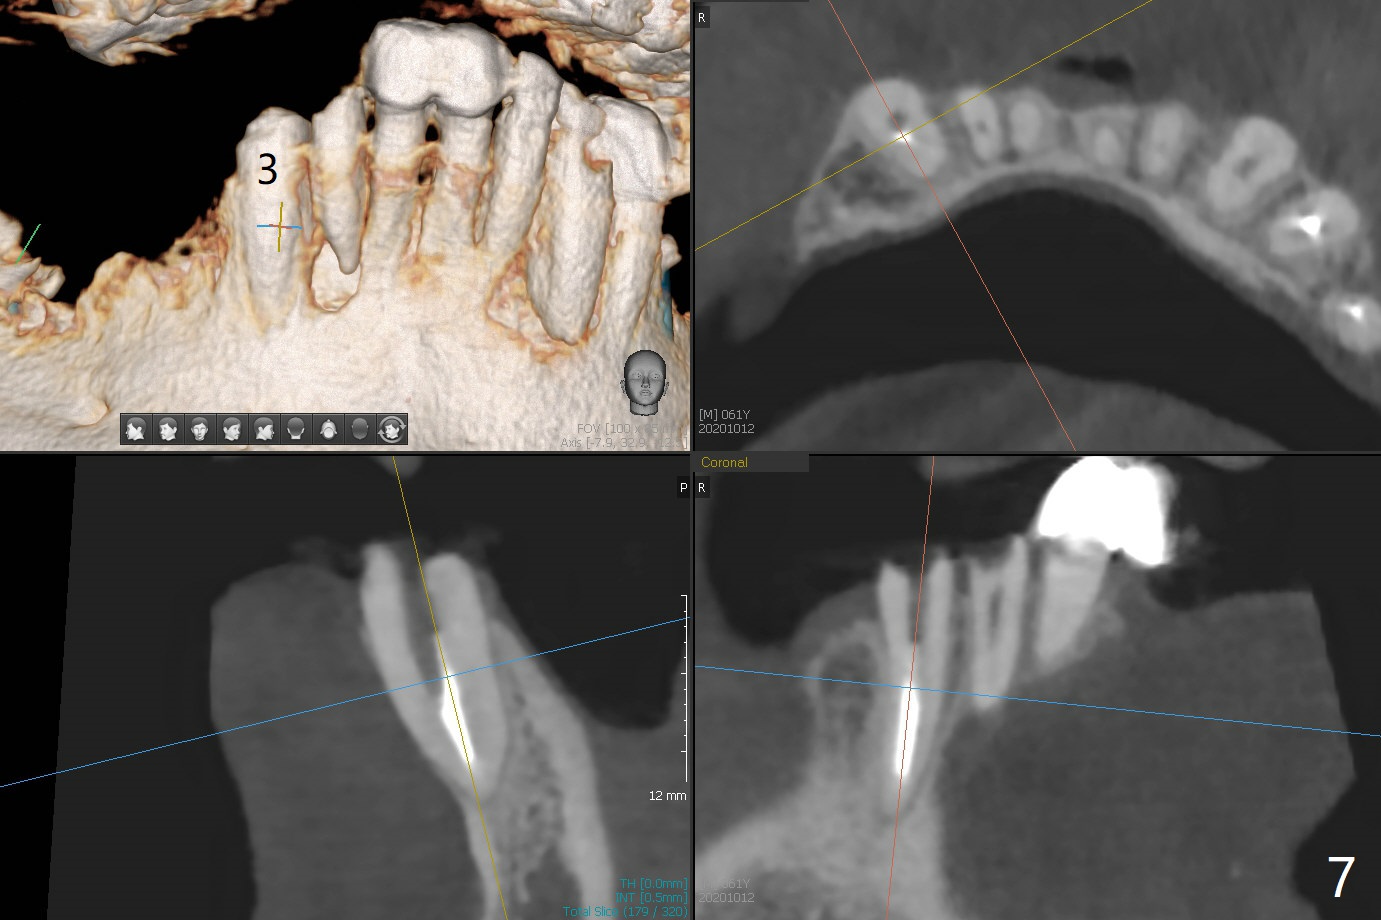

61男牙齿不好,左上4-8牙桥松动(图一,五,六),右下2,左下3根尖瘘道(图二),左上4,8也需要根管治疗,以上牙齿以及右下3插入球状牙桩(图一:*),然后在右上,左下,右下7植牙,放置球状基台(图一:箭头),固定上下活动义齿(覆盖义齿)。下前牙颊侧骨板几乎没有(图七)。左下7骨头(图八)宽于左下5(图三)。